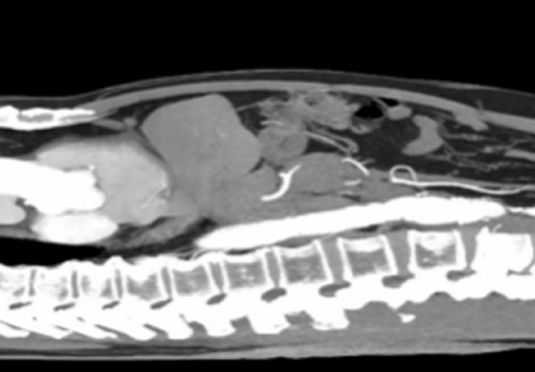

微創射頻消融術